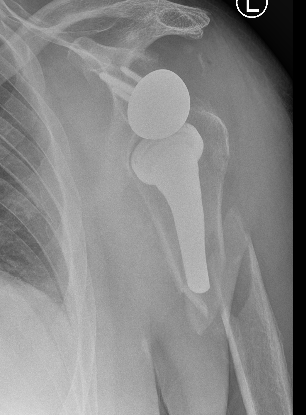

Instability / Dislocation

Dislocated Reverse TSRDislocated Reverse TSR Lateral

disdis